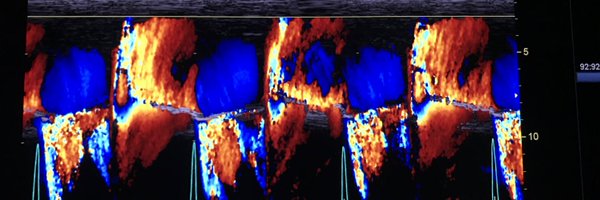

Another successful M-TEER in AFMR case by our team! Mild MR with 2 MitraClip devices! A dedicated session about guiding interventions will explain step-by-step TEER procedures during our 4D echo course! Register and advance your skills in 3DE! @lpbadano https://t.co/K8W7avBnj4

Another MitraClip case in AFMR case done successfully by our team! I am always happy to guide TEER cases!!@fiore_corrado @cardiopole @VDelgadoGarcia @denisamuraru @NAjmoneMarsan @drozgeozden @KemalogluOz @alexsfelixecho @NMerke @DonalErwan @lpbadano @echo_stepbystep @EchoSoliman